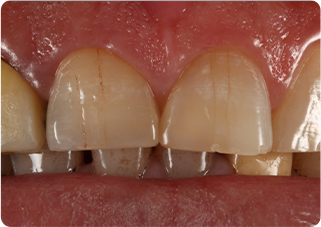

セラミッククラウン症例②

術前

仮歯

術後

| 主訴 | 前歯を綺麗にしたい、隙間が気になる |

|---|---|

| 治療期間/回数 | 4ヵ月、6回 |

| 価格(税込) | 792,000円(税込) |

| リスク・副作用 | セラミック破損の可能性 |

| ポイント | 仮歯で歯ぐきの状態を整え、自然な色、形となるようにオーダーメイドでセラミックを盛り、クラウンを作製した。 |